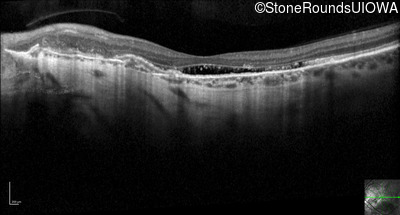

Optical Coherence Tomography - Left - 20/50 -1

Exemplar / OCT Stack